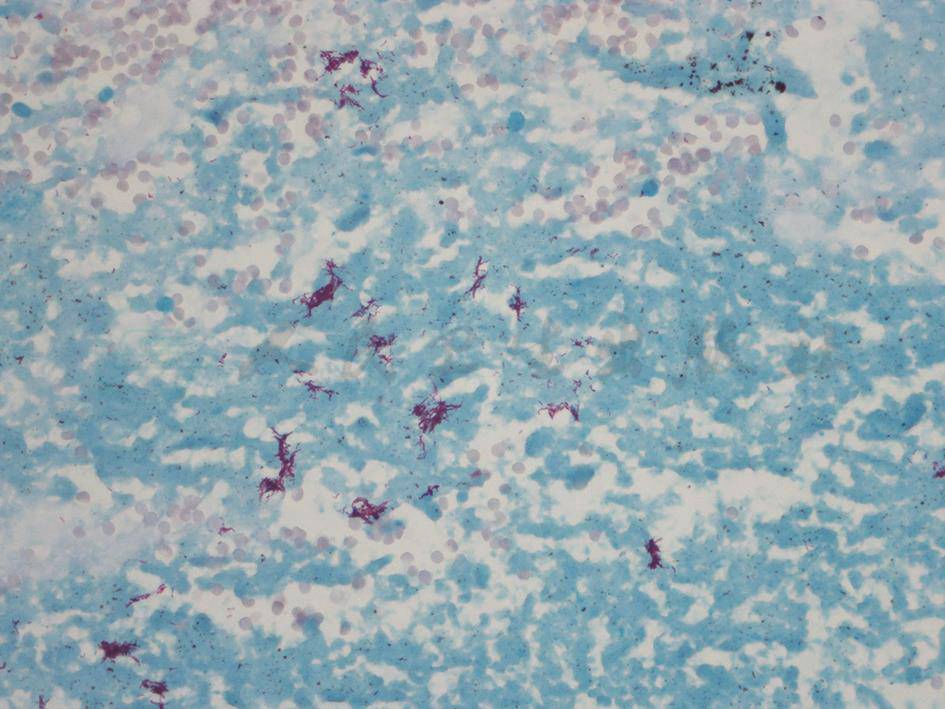

图8 肺组织抗酸染色呈

组织中可见抗酸染色阳性杆菌聚集(抗酸染色,1000×)